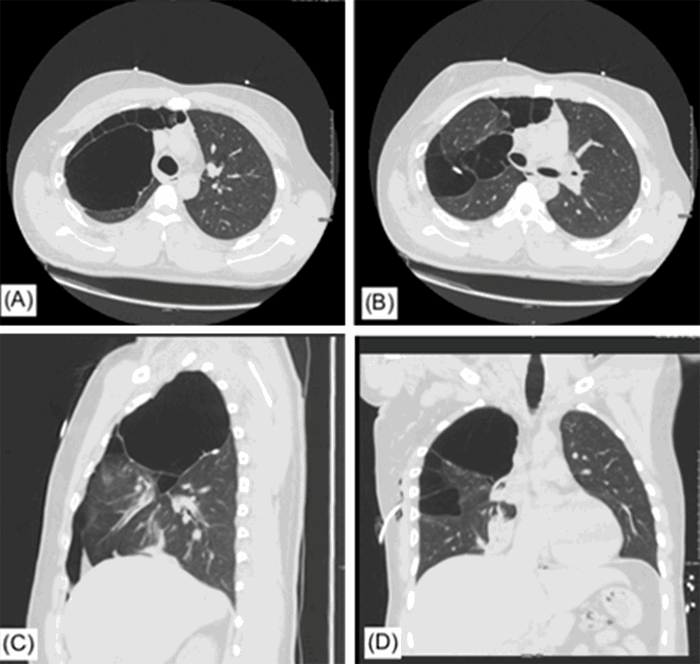

A 29-year-old male presented with acute mid-sternal chest pain associated with dyspnea that was precipitated by a cough after taking “a big hit on his vape,” as indicated by the patient. His past medical history was significant for a diagnosis of asthma and smoking cigarettes and marijuana. He formerly smoked cigarettes at the age of 18 and switched to vaping at the age of 21. He reported a three-pack per year smoking habit for his entire life. On presentation, he was hemodynamically stable despite a large, right-sided pneumothorax found on a chest radiograph (CXR). A right-sided chest tube was immediately placed without any complications. Subsequent computed tomography (CT) scan of the chest demonstrated multiple right upper lobe bullae with one large apical bulla (Figure 1A-D). Notably, the left lobe was free of bullae. After 24 hours on water seal, the chest tube was removed after the morning CXR demonstrated resolution of the pneumothorax. Upon repeat CXR (Figure 2), a recurrence of the right-sided pneumothorax was noted. Interventional radiology was consulted for the placement of a pigtail pleural catheter.

Figure 1. Different views of CT chest with intravenous contrast. Published with permission

The large, apical bullae can be seen. A) Among numerous smaller bullae B) On axial imaging; In the sagittal C) and coronal D) planes, the extent of bullae can be seen in cranial half to right hemithorax while left hemithorax is free of any disease